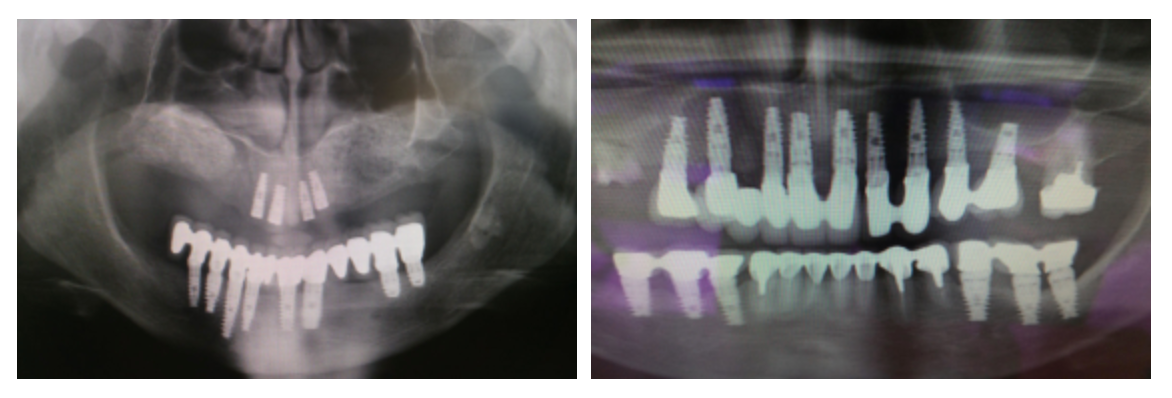

C’est pour cette raison que le praticien adapte la longueur, le diamètre et la forme de l’implant en fonction de chaque cas clinique, en s’appuyant sur des examens radiologiques de haute précision comme l’imagerie 3D ou le scanner.

Le processus commence par la préparation de l’os à l’aide de forets de diamètre adapté. L’implant est inséré avec une légère pression afin d’assurer une bonne stabilité. S’ensuit la phase d’ostéo-intégration, pendant laquelle l’implant, contrairement à une dent naturelle, devient totalement fixe, s’ankylosant dans l’os. Cette étape, cruciale pour le succès de l’intervention, nécessite un délai de plusieurs semaines à plusieurs mois avant la mise en charge définitive.

Enfin, une couronne est placée sur l’implant, qui agit alors comme une racine artificielle, restituant pleinement la fonction et l’esthétique du sourire.

Le Dr Thierry Cattan réalise également des interventions complexes, telles que les greffes de sinus, pour optimiser les conditions de pose des implants.